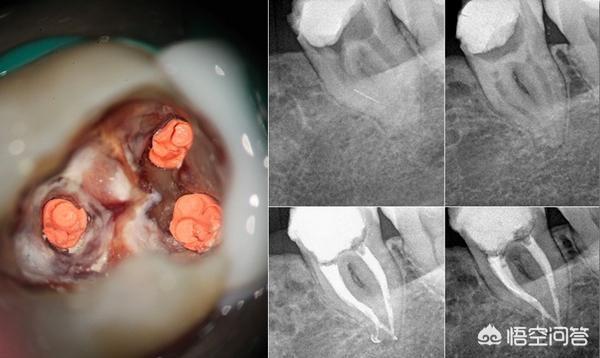

案例介紹 顯微根管 根管慢性發炎與根管鈣化之顯微鏡輔助根管治療 沈庭帆醫師 敦南麗緻牙醫診所

根管治療

钙化根管疏通还没有到底就疼 高手赐教 刘二东的博客 Kq88口腔博客

抽神經要用到顯微鏡 談顯微根管治療 高雄鳳山牙醫診所 壹八八美學牙醫

一例髓腔根管部分钙化的下颌第一磨牙的治疗